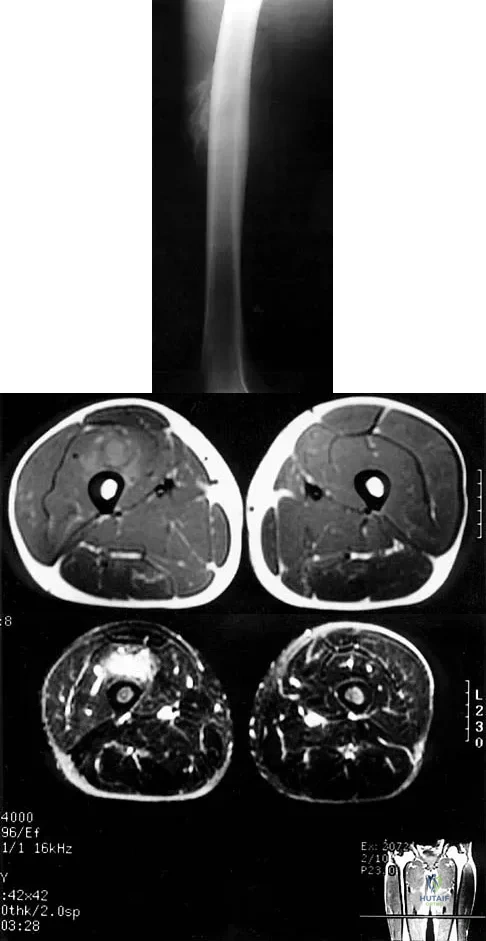

A 36-year-old woman with familial neurofibromatosis has an enlarging mass in the posterior thigh. The lesion has slowly increased in size and is now constantly painful. Pressure on the mass causes dysesthesias in the foot. Figures 44a through 44c show T1-weighted, STIR, and T1-weighted fat-saturated gadolinium scans, respectively. Figure 44d shows a PET scan. What does this lesion most likely represent?

The images reveal a large mass in the posterior thigh arising from the sciatic nerve. The lesion is edematous, and the gadolinium image reveals rim enhancement, suggesting necrosis, given that the STIR image is not uniformly bright as would be seen in a cystic lesion. The PET scan has increased uptake, in this case a standard unit value (SUV) of greater than 2.0. These findings are all very suggestive of a malignant process. The history of neurofibromatosis makes a malignant peripheral nerve sheath tumor, or neurofibrosarcoma, the most likely diagnosis. The term "peripheral nerve sheath tumor" has replaced neurolemmoma and schwannoma. Menendez LR (ed): Orthopaedic Knowledge Update: Musculoskeletal Tumors. Rosemont, IL, American Academy of Orthopaedic Surgeons, 2002, pp 225-230.